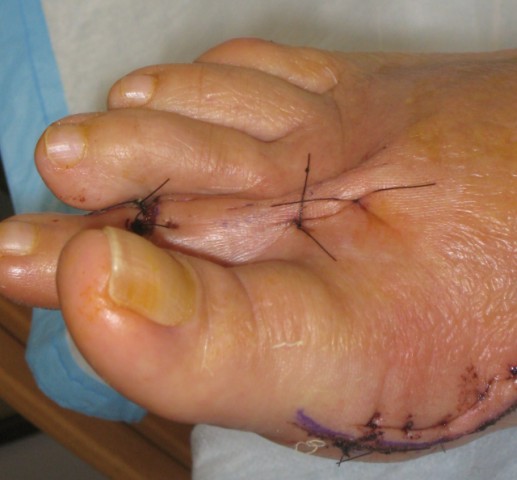

Unfortunately, Betty Lou had experienced this painful sensation before, only this time it was in the right foot – as the "great" toe migrated to the right and deformed the second toe. Doctor Cooper said it was caused by arthritis, and the treatment was the same as before – a bunionectomy, which he performed on September 3rd.

Two weeks later, the sutures

were removed and she was able, carefully, to ambulate with the Geisha boot. However, occasional lunches out and art museum receptions required use of a wheelchair. Until you've been involved in such a situation, you don't realize the ingenuity required to add accessibility to buildings constructed long before such concerns.